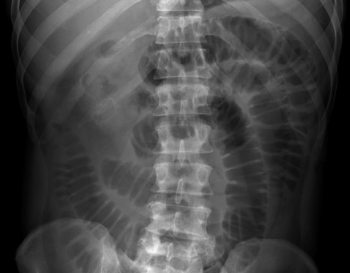

This abdominal X-ray demonstrates multiple dilated loops of bowel with clear valvulae connivente markings. The large bowel is collapsed. **This indicated small bowel obstruction.**